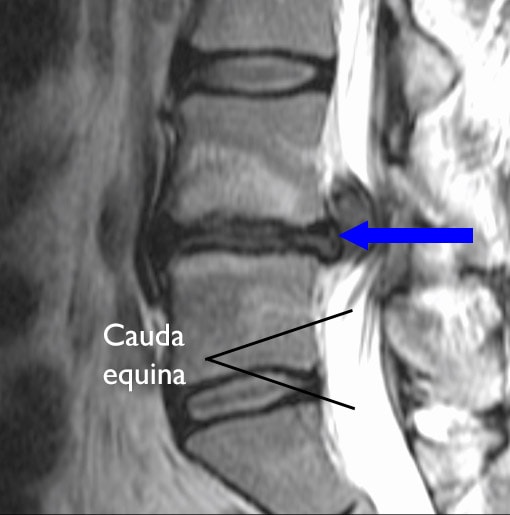

Cauda equina syndrome CES is a condition that occurs when the bundle of nerves below the end of the spinal cord known as the cauda equina is damaged. Cauda equina syndrome CES is a potential consequence of lumbar spinal stenosis LSS that may be under-recognised and consequently poorly managed. Onset may be rapid or gradual.

For some patients cauda equina syndrome CES develops suddenly while other patients experience a gradual onset of symptoms. Cauda equina syndrome CES is a rare condition with a disproportionately high medico-legal profile.